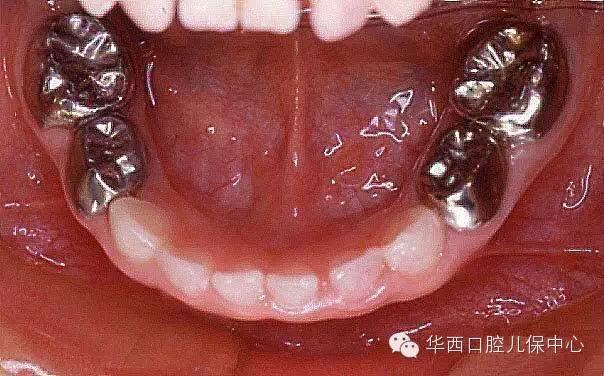

多數(shù)乳磨牙齲壞充填后的金屬預(yù)成冠修復(fù)